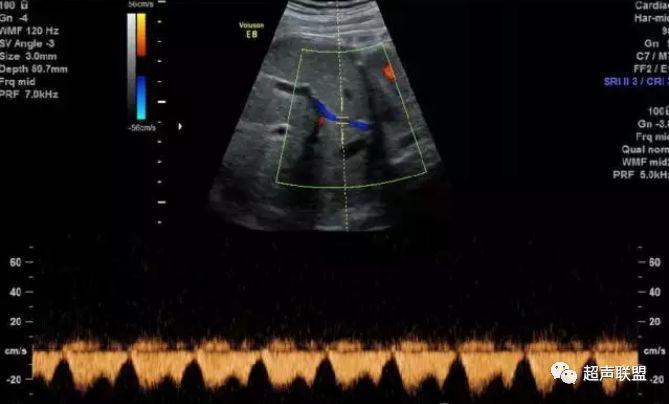

2 胎儿大脑中动脉测定

缺氧早期大脑血液供应增加,颅内血管扩张,阻力降低,舒张末期血流速度增加,PI、RI值下降,说明缺氧早期的血流再分配。当大脑中动脉RI、PI值明显下降,而脐动脉和腹主动脉的PI值升高,大脑中动脉PI值与脐动脉PI值的比值低于2个标准差时,提示严重缺氧的存在。

1、比值标准:大脑中动脉阻力降低,妊娠期,大脑中动脉RI <脐动脉RI;

4、当大脑中动脉RI及PI值明显下降,而脐动脉及腹主动脉的PI值之间升高,大脑中动脉PI值与脐动脉PI值低于两个标准差时,提示为胎儿严重缺氧;

图3 正常大脑中动脉血流频谱

图4 大脑中动脉血流阻力减低